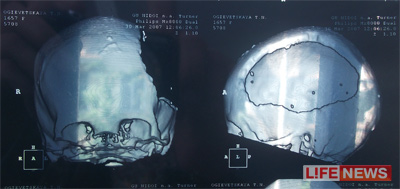

- Я хорошо помню тот зимний день и ту операцию, - рассказывает врач Николай Коршунов. - Нам пришлось полностью удалить все левое полушарие девочки, которое отвечает за логику, анализ, контролирует речь. Надежды, что она выживет, практически не было.

В голову пациентке вставили пластину, благодаря которой она смогла выжить.